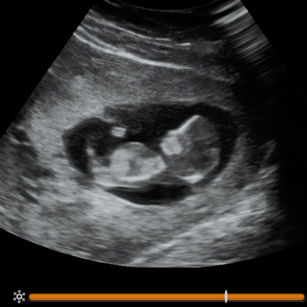

11 Weeks Pregnant

Size: ~1.5 inches (4 cm), the size of a Fig!

Nervous system growing; reflexes begin.

Eyes, nose, mouth, and ears more distinct.

Baby can make small movements of head and limbs.